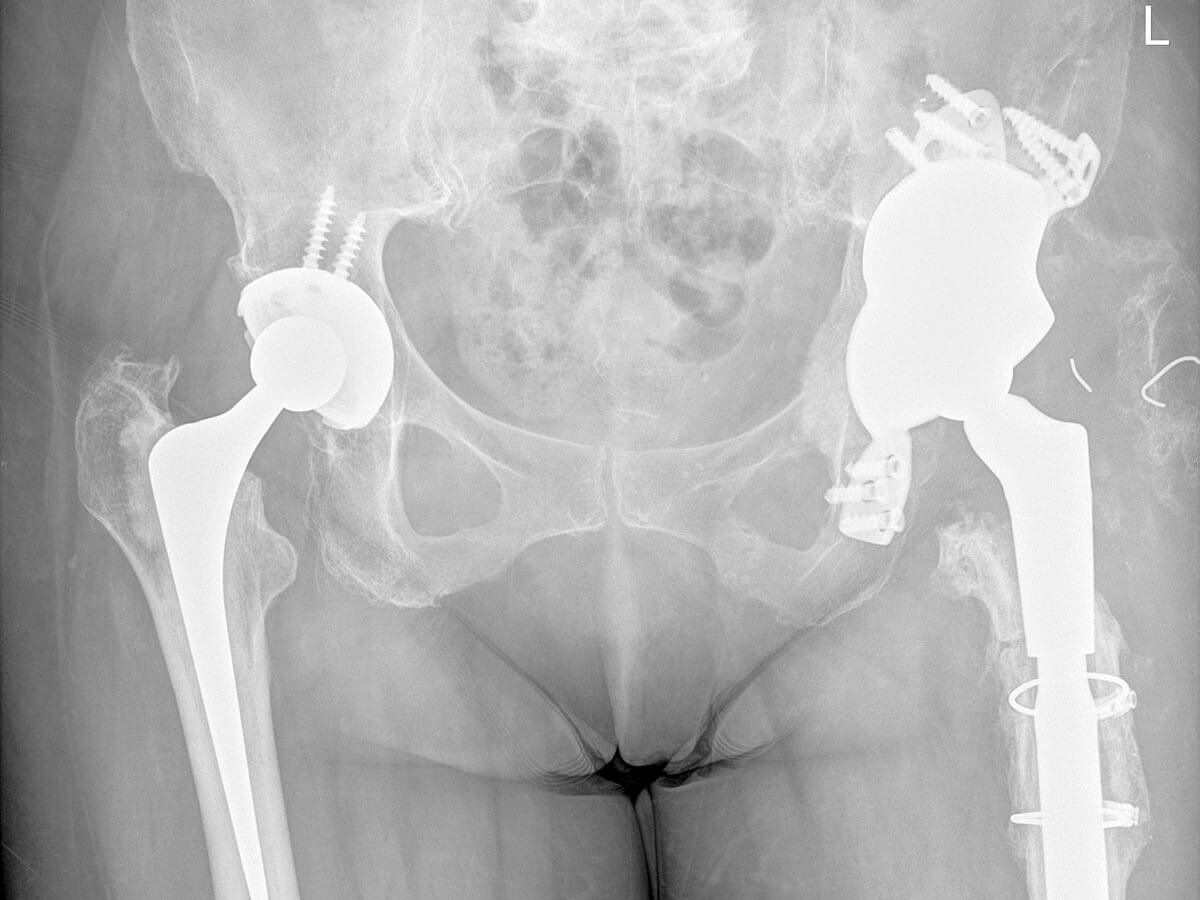

Occasionally, a primary hip replacement may require revision due to persistent pain, implant wear, instability, loosening, fracture, or infection. Revision hip replacement surgery involves the careful removal and replacement of one or more components of the original hip prosthesis.

Depending on your individual condition, this procedure may also require the reconstruction of bone or soft tissue using bone grafts, augments, or specialised revision implants designed to restore stability and function. In cases of infection, a staged approach may be necessary, involving temporary spacers and antibiotic treatment before reimplantation.

Revision hip replacement is technically more complex than a primary procedure, requiring advanced surgical planning, careful handling of bone and soft tissues, and the use of specialised implants. Dr Jason Hockings has extensive experience in revision hip arthroplasty and will tailor your surgical plan to address your unique anatomy, diagnosis, and previous surgical history.

Surgical options: Types of revision hip procedures

The type of revision hip replacement you may require depends on which part of the original prosthesis is failing, as well as the extent of bone loss, infection, or implant wear. Revision surgery is tailored to each patient and can range from minor adjustments to complete reconstruction of the hip joint.

In cases where both the femoral and acetabular components are failing, a full revision may be required. This involves replacing the entire hip prosthesis and may include reconstructive techniques to address bone defects.